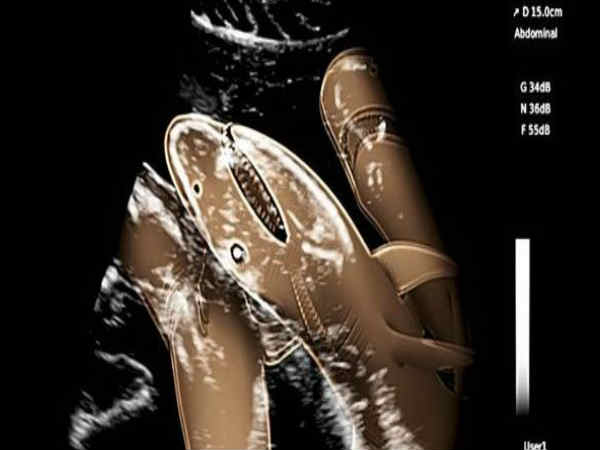

ಕಡಲ ವಿಜ್ಞಾನಿಗಳು ಇದುವರೆಗೆ ಯಾರೂ ಮಾಡದೇ ಇರುವ ಸಾಹಸವೊಂದಕ್ಕೆ ಕೈಹಾಕಿದ್ದು 12.5 ಫೀಟ್ ಉದ್ದದ ಟೈಗರ್ ಶಾರ್ಕ್ನ ಸೊನೊಗ್ರಾಮ್ ಅನ್ನು ಮಾಡಿದ್ದು ವೈಜ್ಞಾನಿಕ ಸಾಹಸವಾಗಿ ಅಂಗೀಕೃತವಾಗಿದೆ.

ನ್ಯೂ ಇಂಗ್ಲೇಂಡ್ನ ಜೇಮ್ಸ್ ಸುಲುಕೊವಿಸ್ಕಿ ಮತ್ತು ಮಿಯಾಮಿ ಯೂನಿವರರ್ಸಿಟಿಯ ನೇಲ್ ಹ್ಯಾಮರ್ ಶ್ಲಾಗ್ ಇಮಿಲಿ ಹೆಸರಿನ ಶಾರ್ಕ್ ಮೇಲೆ ಈ ಪ್ರಯೋಗವನ್ನು ನಡೆಸಿದ್ದು, ಈ ತಳಿಗಳು ಸಾಮಾನ್ಯವಾಗಿರುವ ಬಹಾಮಾದಲ್ಲಿ ಪ್ರಯೋಗ ನಡೆಸಲಾಗಿದೆ. ಸೊನೊಗ್ರಾಮ್ನಲ್ಲಿ ಪತ್ತೆಯಾಗಿರುವ ಸಂಗತಿ ಎಂದರೆ ಶಾರ್ಕ್ 20 ಮರಿಗಳನ್ನು ತನ್ನಲ್ಲಿ ಹೊಂದಿದ್ದು ಇದು ಬಾಯಿ ತುಂಬಾ ಹಲ್ಲುಗಳನ್ನು ಪಡೆದುಕೊಂಡಿದೆ ಎಂದಾಗಿದೆ. ಈ ಕುರಿತು ಇನ್ನಷ್ಟು ಮಾಹಿತಿಯನ್ನು ಈ ಕೆಳಗಿನ ಸ್ಲೈಡರ್ಗಳಲ್ಲಿ ನಾವು ನೀಡುತ್ತಿದ್ದೇವೆ.

ಸೊನೊಗ್ರಾಮ್

ಗರ್ಭಿಣಿ ಶಾರ್ಕ್ ಮೇಲೆ ಸೊನೊಗ್ರಾಮ್ ನಡೆಸಿರುವ ವಿಜ್ಞಾನಿಗಳು ಅಪರೂಪದ ಪ್ರಕ್ರಿಯೆಯನ್ನು ಕೈಗೊಂಡಿದ್ದಾರೆ. ಅದೂ ಜೀವಂತವಾಗಿರುವ ಶಾರ್ಕ್ ಮೇಲೆ ಈ ಪ್ರಯೋಗವನ್ನು ನಡೆಸಿ ಇವರುಗಳು ಅದರಲ್ಲಿ ಯಶಸ್ಸನ್ನು ಪಡೆದುಕೊಂಡಿದ್ದಾರೆ.

ಶಾರ್ಕ್ ಹೊಟ್ಟೆಯೊಳಗೆ ಮರಿ ಶಾರ್ಕ್ಗಳನ್ನು ಸ್ಪಷ್ಟವಾಗಿ ಈ ಪರೀಕ್ಷೆಯು ತೋರಿಸಿದ್ದು, ಅವುಗಳು ಹೊಟ್ಟೆಯಲ್ಲಿ ಯಾವ ರೀತಿಯಲ್ಲಿ ಚಲಿಸುತ್ತಿವೆ ಎಂಬುದರ ವೀಡಿಯೊ ಪ್ರಕಟವಾಗಿದೆ.